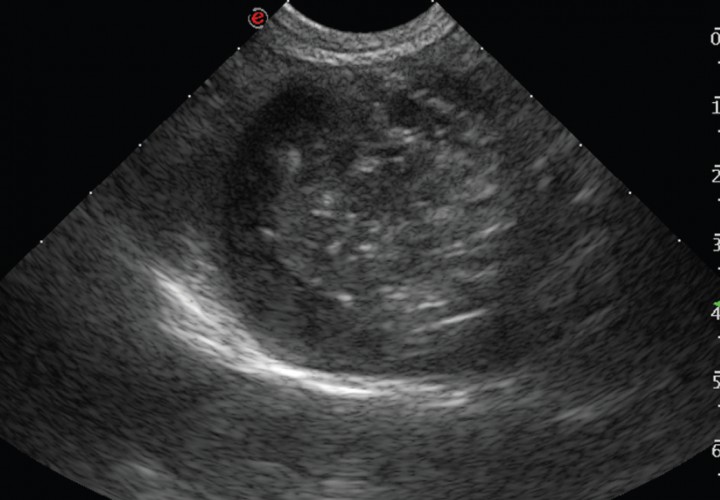

El examen ecográfico fue realizado con sondas semiconvex (3-9 MHz) o lineales (4-13 MHz) (Esaote, Mylab 70, Barcelona, España) según el tamaño del paciente; los animales se posicionaban en decúbito lateral, supino o en estación para confirmar que el contenido de la vesícula biliar era inmóvil. En el examen ecográfico se evaluó el modelo del contenido biliar, grosor de la pared (normal < 3 mm),[ Spaulding KA. Ultrasound corner: Gallbladder Wall thickness. Vet Radiol & Ultrasound 1993; 34:270-272. ] aspecto del tejido adyacente a la vesícula, ecogenicidad del hígado (normal, hiperecogénico, hipoecogénico, o heterogéneo), si existía efusión peritoneal y alteraciones ecográficas en otros órganos. El grado de distensión de la vesícula biliar se evaluó en corte longitudinal (valores de referencia: longitud 3–7,8 cm y profundidad 1,4–4,3 cm) y en corte transversal (valores de referencia: anchura 1,8–4,9 cm y profundidad 1,5–4,1 cm).[ Atalan G, Barr FJ, Holt PE: Estimation of the volumen of the gall bladder of 32 dogs from linear ultrasonographic measurements. Vet Rec, 2007;160: 118-122. [PubMed] ] El modelo del contenido de la vesícula biliar se dividió en 5 tipos (clasificación modificada de JG Besso[ Besso JG, Wrigley RH, Gliatto JM, Webster CRL: Ultrasonographic appearance and clinical fidings in 14 dogs with mucocele. Vet Radiol & Ultrasound, 2000; 41: 261-271. [PubMed] ] y J Choi[ Choi J, Kim A, Keh S, Oh J, Kim H, Yoon J. Comparison between ultrasonographic and clinical fidings in 43 dogs with gallbladder mucoceles. Vet Radiol & Ultrasound, 2014; 55:202-207. [PubMed] ]): Tipo I, sedimento ecogénico inmóvil (Fig. 1); Tipo II, patrón estriado (sedimento ecogénico inmóvil en el que se visualizan estriaciones hipoecogénicas finas y mal definidas desde el interior hacia la pared de la vesícula; Fig. 2); Tipo III, en forma de estrella (material ecogénico en el centro de la luz vesical que emite prolongaciones hipoecogénicas hacia la periferia presentando forma de estrella; Fig. 3); Tipo IV, combinación de patrón de kiwi-estrella (sedimento ecogénico ocupando la zona central de la vesícula biliar en donde se producen prolongaciones con finas estriaciones hacia la periferia; Fig. 4), Tipo V, modelo de kiwi (material ecogénico inmóvil con finas estriaciones hipoecogénicas atravesándolo y ocupando el centro de la luz vesical; Fig. 5).

<p>Imagen ecográfica de la vesícula biliar en corte transversal. Modelo de mucocele biliar de Tipo III: la vesícula biliar se observa distendida con contenido ecogénico inmóvil en su interior adherido a la pared y material ecogénico en el centro que emite prolongaciones hipoecogénicas hacia la periferia presentando una forma de estrella.</p>

Figura 3

Imagen ecográfica de la vesícula biliar en corte transversal. Modelo de mucocele biliar de Tipo III: la vesícula biliar se observa distendida con contenido ecogénico inmóvil en su interior adherido a la pared y material ecogénico en el centro que emite prolongaciones hipoecogénicas hacia la periferia presentando una forma de estrella.